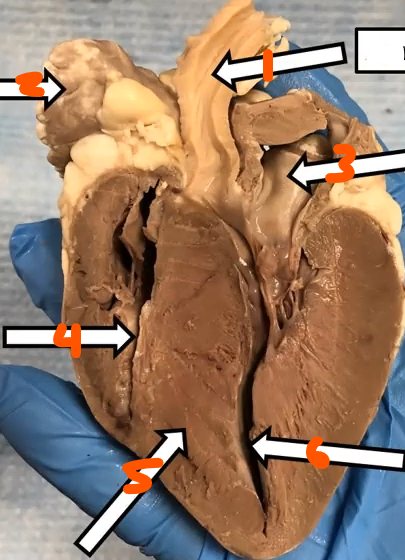

3. left atriumright ventricle

interventricular septum

left ventricle

What is this

moderator band

Top

2. Bottom

Mitral valve

Chordae tendinae